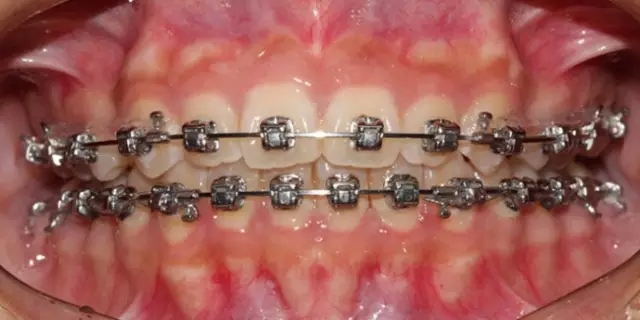

Damon 病例分享:安氏 II 類(lèi)二分類(lèi)露齦笑的矯治(董一磊)

治療前后對(duì)比